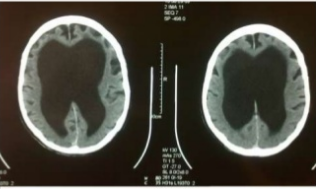

2. INTERSTICIAL

1. También conocido como edema celular o edema oncótico, es el resultado de cualquier lesión celular que conlleve a la falla energética en la que la bomba Na+K+ ATPasa no cuenta con suficiente capacidad para mantener los gradientes iónicos celulares, por lo que ocurre un influjo anómalo de sodio y agua hacia la célula modificando la homeostasia intra y extracelular

1. -Hidrrocefalia obstructiva -Hidrocefalia no obstructiva